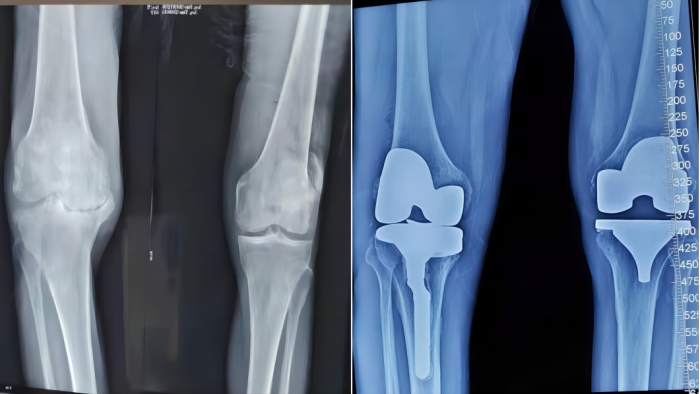

人工膝关节置换术